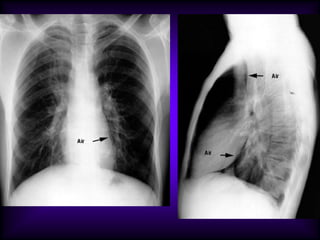

Upper lobe Bulla

Lower lobe Bulla

A: Xray shows bilateral bulla.

B: CT shows bilateral bulla.

C: CT after bullectomy.